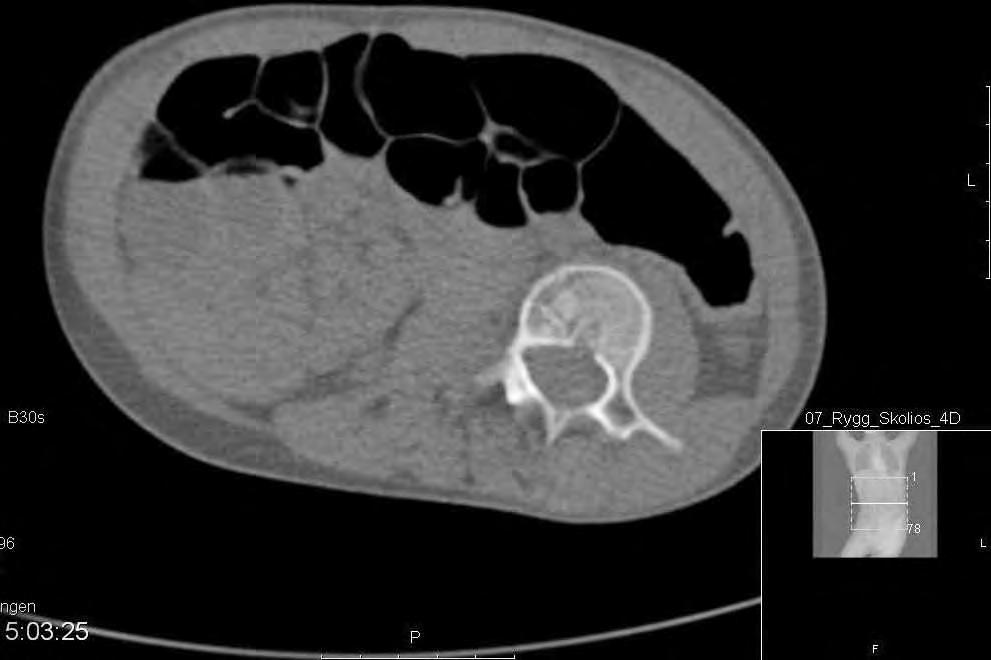

CT-lågdos med axialt snitt L3 preop visande 18 graders rotation enl. Aaro.

CT-lågdos med axialt i L3, postop visande reduktion av rotatione till 8 grader. Man ser också att kotkroppen ligger mer centralt i torson.